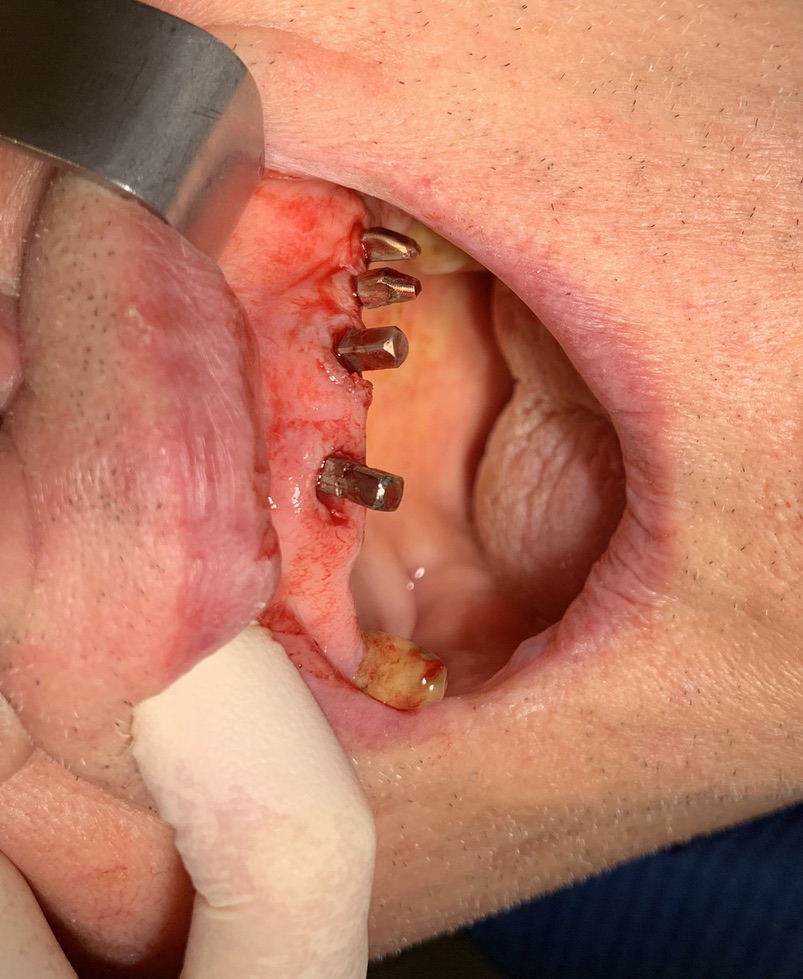

Data: 09/01/2020    Ambulatorio: Guidizzolo     Cognome e nome: Xxxxxxxxx Xxxxxx    Età:  88

Numero impianti esistenti: 3     Data e numero degli interventi: nel 1993 3 impianti in zona 14  24  25

Tipo di impianto: Tramonte     Numero di impianti inseriti: 2     Saldatura: No    Zona dentale: 21   23

App.Rx Endorale:Vix Win     Tac: No     Situazione estrattiva:  impianti postestrattivi immediati   Densità Secondo Misch: D2

Operatore 1:  Dr. Bellini    Operatore 2: Dr. Bazzoli     Sequenza frese: Solo fresa lanceolata    Sequenza maschiatori: solo diametro 4 mm.

Carico occlusale: Immediato      Complicanze:      Video o dichiarazione scritta di soddisfazione.